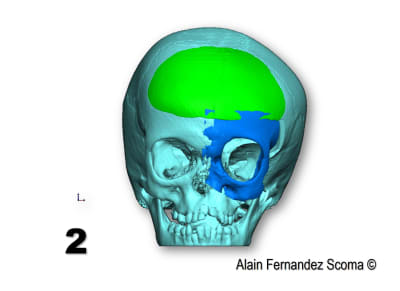

Tien un exemple d'une commande par un Professeur en maxillo- qui me demande : " Alain, tu peux étudier comment segmenter ce massif facial (1) pour reconstruire une forme correcte (2)". Le jour de chirurgie (3) ils sont utilisé un guide de coupe (4)pour tracer les segments et découper la calotte crânienne (5)l'arcade orbitaire... et réorganiser (6) les tronçons. Le scan de contrôle (7) superposé sur l'étude (8) montrent la pertinence du partage. Il y a une découpe dont le tracé à était modifié par rapport à l'étude ce qui m'a fait plaisir de voir justesse d'analyse du chirurgien.